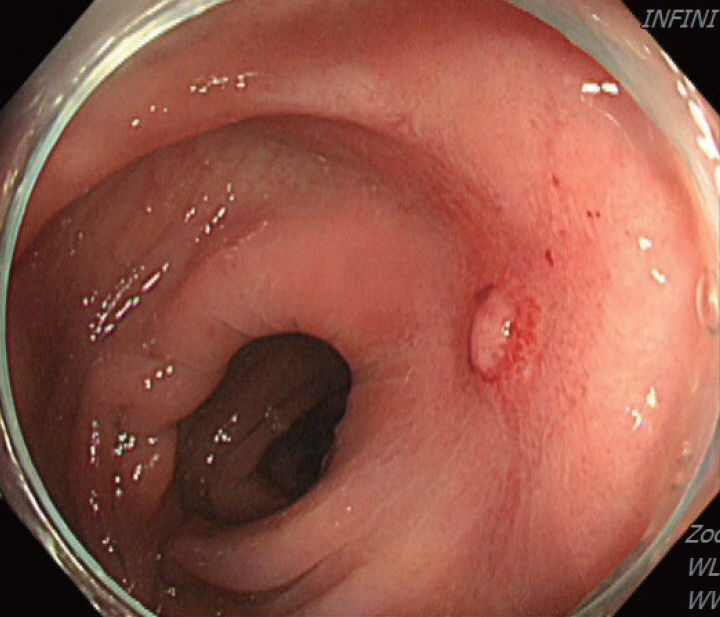

A 70-year-old male underwent sigmoidoscopy after a routine computed tomography (CT) examination, which showed thickening of the sigmoid wall (Fig. 1). Sigmoidoscopy revealed a colonic ulcer, and a biopsy was performed. The lesion was identified as a tubular adenoma; therefore, the patient was referred to the gastroenterology department for repeat biopsy and additional tests. The patient’s medical history included high blood pressure and alcoholic hepatitis. His social history showed that he drank 0.5-1.0 bottle of soju daily and was never a smoker. Information regarding his family history was excluded from the study. The patient had no gastrointestinal symptoms such as abdominal pain or diarrhea, and physical examination findings were unremarkable. Although the biopsy showed a tubular adenoma, the initial colonoscopy indicated that the gross margin of the ulcer was irregularly shaped (Fig. 2), raising suspicion for malignancy. Therefore, despite being asymptomatic, the patient was informed, and another colonoscopy was performed 2 months later. The follow-up examination revealed a scarred sigmoid ulcer located 30 cm from the anal verge, which seemed to have improved compared with the previous findings. Re-biopsy demonstrated features consistent with a simple ulcer (Fig. 3). Accordingly, we concluded that this was a benign colonic ulcer with an inflammatory and ischemic cause rather than cancer, and a follow-up CT scan was sche-duled 1 month later. At the follow-up visit 1 month later, the patient complained of abdominal discomfort after eating for a week, which had not occurred before. He denied having fever, chills, nausea, or vomiting. A subsequent abdominal CT scan showed an approximately 9-cm cavitary lesion abutting the sigmoid colon and urinary bladder dome in the small intestine (Fig. 4). This was accompanied by diffuse nodular omentomesenteric infiltration and peritoneal thickening with small ascites. Based on these findings, the patient was suspected to have a malignant tumor, such as scirrhous carcinoma, inflammatory bowel disease, peritoneal carcinomatosis, or peritonitis, and was referred to a surgeon for surgical treatment. The patient was hospitalized immediately. On admission, the patient complained of abdominal discomfort after eating, and mild generalized abdominal tenderness was noted on physical examination. He was hemodynamically stable. Laboratory testing revealed high white blood cell count of 11.45 × 103/μL (normal range, 4.0-10.0 × 103/μL) with a differential of 67.6% neutrophils (normal range, 38.0-75.0), normal hemoglobin of 16.1 g/dL (normal range, 13.0-17.0), normal platelet count of 151 × 103/μL (normal range, 150-400 × 103/μL), and slightly elevated C-reactive protein level of 7.69 mg/L (normal range, 0.0-5.0). Serum electrolyte and kidney function test results were normal. On the 3rd day of hospitalization, the patient underwent laparoscopic small bowel resection. Immunohistochemical analysis of the resected tissue showed positive staining for CD3, CD4, CD8, CD56, and CAM 5.2 (epithelial marker), and a negative staining for CD10, CD20, CD21, and CD30 (Fig. 5). Histopathological evaluation revealed infiltration by small- to medium-sized T-cell with prominent epitheliotropism, consistent with MEITL. The final diagnosis was MEITL, involving the sigmoid colon, urinary bladder, and peritoneum. Postoperatively, the patient developed persistent ileus with progressive ab-dominal distension and loss of bowel passage, necessitating a second emergency surgery on the 20th day of hospitalization. On the 25th day of hospitalization, the Hemovac drainage became purulent, blood pressure decreased, and the patient went into shock; therefore, a third emergency surgery was performed under the suspicion of bowel perforation. On the 45th day of hospitalization, the patient died of refractory septic shock, presumed to be a complication of intestinal perforation.

Figure 2.

Initial colonoscopy showing an irregularly shaped gross margin of the ulcer.